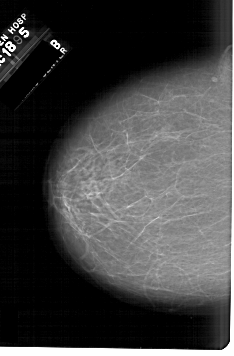

A_1633_1.RIGHT_MLO

RIGHT_MLO LINES 6136 PIXELS_PER_LINE 4081 BITS_PER_PIXEL 12 RESOLUTION 43.5 OVERLAY